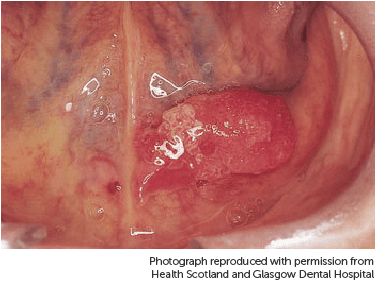

The pictures below show cancer on the side of the tongue.